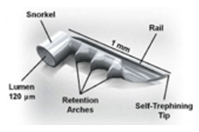

最近では白内障同時の極低侵襲緑内障手術 iStent手術(右)が保険診療で手術ができるように認定されました。

その他CTR手術(左)・瞳孔形成術・眼内レンズ入替術・裂孔閉鎖術・Add-onレンズ挿入術・眼内レンズ回転術など手術をいろいろなデバイスや術式で行っております。